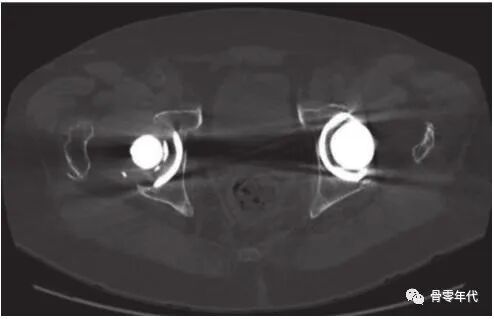

2.4CT检查:对于隐匿性的骨折,建议使用CT诊断,Y oshimi Endo等人报告了两个病例,其中陶瓷内衬骨折在放射学上是隐匿性的,但在随后的CT扫描中被诊断出来。并建议对植入陶瓷假体后出现疼痛和/或吱吱声的患者进行CT成像,因为这可能是陶瓷断裂的迹象。但Roozbeh等人认为CT对破裂的衬垫进行成像时,金属伪影可能会降低CT检测隐匿性线性骨折的敏感性。

髋关节置换衬垫骨折的CT征象